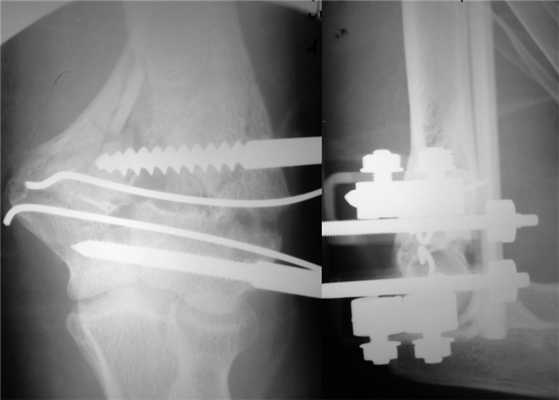

На следующий день под новокаиновым блоком плечевого сплетения произведена операция: закрытая репозиция и чрескостный остеосинтез левой плечевой кости спице-стержневым аппаратом внешней фиксации конструкции А.И. Городниченко. Через разрезы кожи и мягких тканей по наружной поверхности левого плеча длиной до 5 мм введено 2 кортикальных стержня в диафиз плечевой кости, один кортикальный и один спонгиозный стержень и 2 спицы с упорной площадкой в мыщелки и надмыщелки плечевой кости. После фиксации проксимальных стержней в аппарате под контролем электронно-оптического преобразователя произведена закрытая репозиция с помощью съемных рукояток с последующей стабилизацией дистальных стержней и спиц (рис. 3). Рисунок 3. Рентгенограммы больной П. после остеосинтеза левой плечевой кости спице-стержневым аппаратом. Кожа вокруг стержней ушита одиночными швами. Кровопотеря в ходе операции 20 мл. Продолжительность операции 40 мин.

Послеоперационное течение без осложнений, проводили регулярные перевязки с обработкой кожи вокруг стержней и спиц растворами антисептиков и сменой асептических повязок. Швы вокруг стержней сняты через 8 дней после операции, пациентка выписана на амбулаторное лечение с рекомендациями по дальнейшему восстановительному лечению. Движения в левом локтевом суставе перед выпиской из стационара показаны на рис. 4. Рисунок 4. Рентгенограммы больной П. после остеосинтеза левой плечевой кости спице-стержневым аппаратом.

После консолидации перелома через 71 день произведен демонтаж аппарата (рис. 5). Рисунок 5. Рентгенограммы больной П. после остеосинтеза левой плечевой кости спице-стержневым аппаратом. Движения в левом локтевом суставе после демонтажа аппарата от 0 до 128° (рис. 6). Рисунок 6. Внешний вид больной П. после демонтажа аппарата (объем движений в левом локтевом суставе от 0 до 128°).